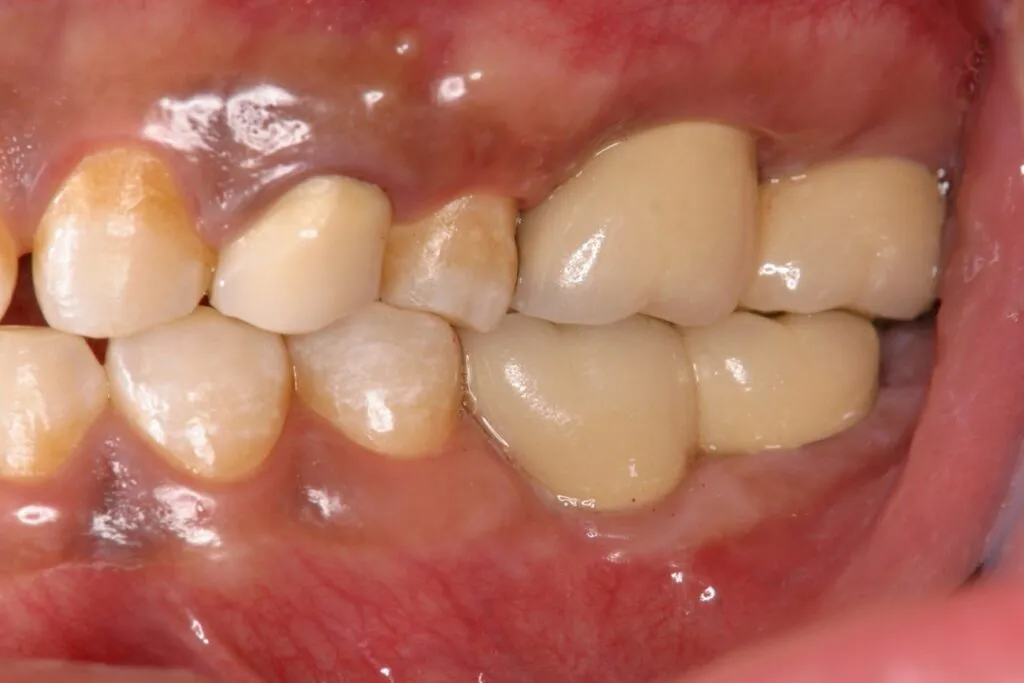

症例⑦

| 主訴 | 残根状態 歯を入れたい |

| 診断名 | 咀嚼障害 |

| 年齢 | 29歳 |

治療に用いた装置(治療法) | インプラント |

| 部位 | 左上6・左上7・左下6・左下7 |

| 治療期間 | 8か月 |

| 治療費用 | 1,848,000円 |

| リスク・副作用(治療に関する) | 腫脹、しびれ |